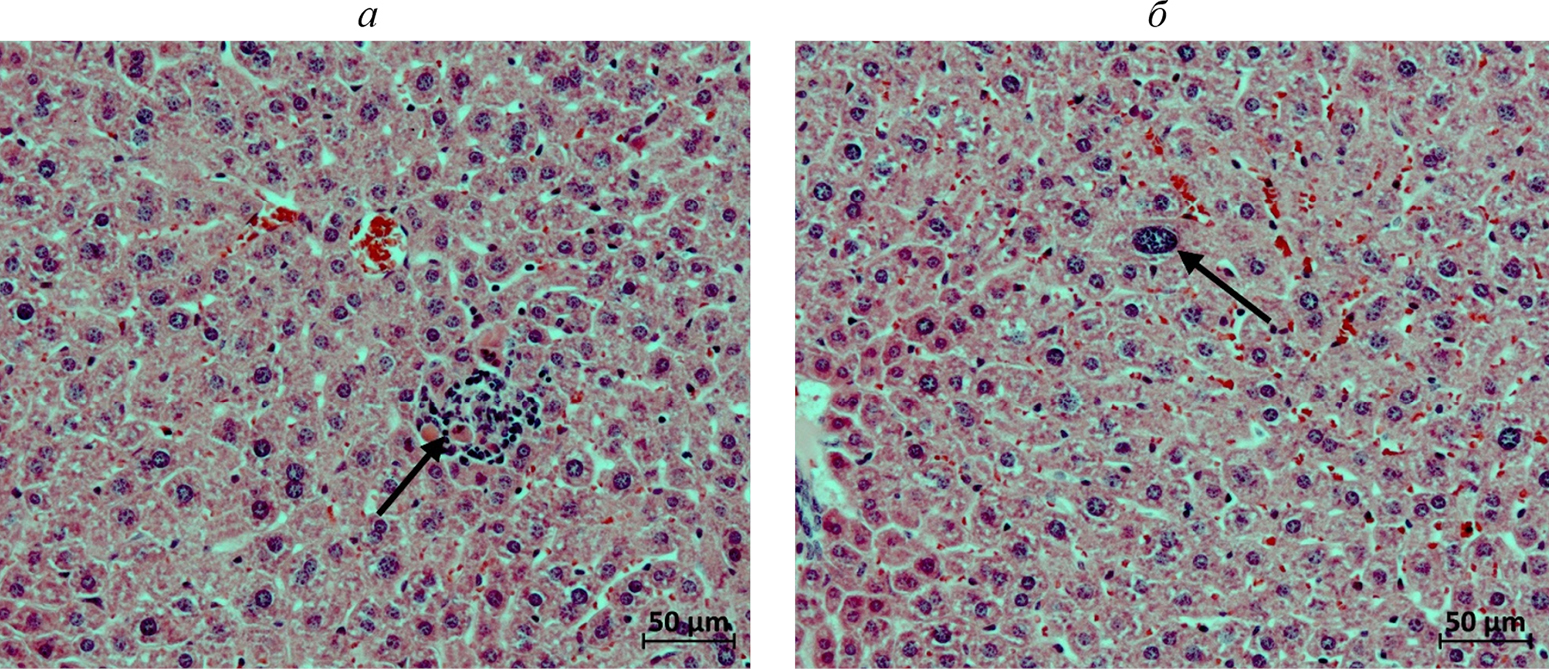

Острая токсичность. Печень. У мышей контрольной группы на 7-й день после однократного введения физраствора в паренхиме печени находили единичные мелкие очаги мононуклеарной инфильтрации (рис. 2а). В одном случае отмечали очаговую гипертрофию гепатоцитов (рис. 2б). В группе введения однократной дозы препарата практически у всех животных в печеночной паренхиме обнаруживали многочисленные мелкие очаги мононуклеарной инфильтрации на месте погибших гепатоцитов с поздними проявлениями их фагоцитоза (рис. 3а) (табл. 2). У двух мышей данной группы отмечали очаговую гипертрофию гепатоцитов, у одной – единичные случаи кариомегалии гепатоцитов (рис. 3б). В группе введения пятикратной дозы препарата у двух животных в печеночной паренхиме находили также немногочисленные очаги нейтрофильной инфильтрации (рис. 4а), еще в двух случаях в очагах мононуклеарной инфильтрации присутствовали сегментоядерные лейкоциты (рис. 4б). В группе введения 10-кратной дозы препарата в печени встречали те же изменения, что и при введении тестируемого вещества в дозировке ×5. Вместе с тем, у двух животных данной группы в печени находили мелкие свежие очаги гепатоцитов с начальными явлениями некроза (рис. 5а). Еще у одной мыши в одной из долей органа наблюдали единичные гепатоциты с пигментными включениями в цитоплазме (рис. 5б).

Рис. 2. Фрагменты печени самок мышей контрольной группы. Окраска гематоксилином и эозином. Стрелками указаны: а – мелкий очаг мононуклеарной инфильтрации в паренхиме одной из долей органа (мышь 5.1); б – гипертрофия отдельных гепатоцитов (мышь 5.2).

Рис. 3. Фрагменты печени самок мышей на 7-й день после однократного введения 1.5 Ед С115Н-PIC-сом МГЛ/2 мг метиина. Окраска гематоксилином и эозином. Стрелками указаны: а – мелкий очаг мононуклеарной инфильтрации в паренхиме одной из долей органа (мышь 1.2); б – кариомегалия гепатоцита (мышь 1.3).

Рис. 4. Фрагменты печени самок мышей на 7-й день после однократного введения 1.5 Ед С115Н-PIC-сом МГЛ / 10 мг метиина. Окраска гематоксилином и эозином. Стрелками указаны: а – мелкие очаги инфильтрации сегментоядерными лейкоцитами (мышь 2.1), б – очаг мононуклеарной инфильтрации с единичными сегментоядерными лейкоцитами и явлениями фагоцитоза погибших гепатоцитов (мышь 2.6).

Рис. 5. Фрагменты печени самок мышей на 7-й день после однократного введения 1.5 Ед С115Н-PIC-сом МГЛ/20 мг метиина. Окраска гематоксилином и эозином. Стрелками указаны: а – очаг гепатоцитов с начальными явлениями некроза (мышь 3.4), б – гепатоциты с пигментными включениями в цитоплазме (мышь 3.5).

Таким образом, проведенное гистологическое исследование выявило слабое/умеренное дозозависимое гепатотоксическое действие однократного введения тестируемого препарата, проявляющееся, прежде всего, в мелкоочаговой гибели гепатоцитов.